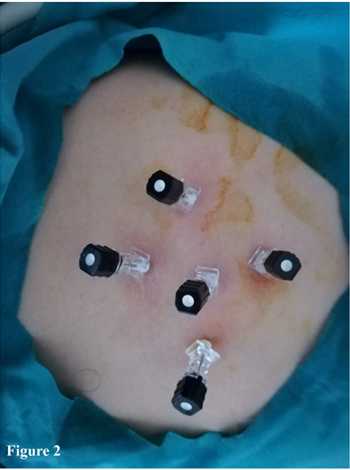

All procedures were performed under sonographic guidance in the ultrasonography unit of a gastroenterology department that was fully equipped against an emergency condition. An intravenous line was established. The patients were positioned according to the location of the cysts as left lateral, right lateral or supine position. All patients were given 5mg of meperidine and 40mg methyl prednisolone as sedo-analgesia just before the procedure. The percutaneous puncture was performed under sonographic guidance using a 22-gauge Chiba needle as a one-step procedure in CE type 1 and 3A. However, two to six Chiba needles were used in different locations at the same time in the cyst of CE type 2, 3A and 3B (Figure 2). For every 1 cm of the long diameter of the cyst lesion, 3cc of fluid from the cysts was aspirated, which was almost the same amount of cc in volume for the CE type 1 or Gharbi type 1 and CE type 3A or Gharbi type 2 hydatid cysts. A 2cc of pure alcohol (96 %) and 1cc of polidocanol 1% (ethoxysclerol 1%, Kreussler Pharma, Wiesbaden, Germany) were injected into the cysts right after the aspiration of CE type 1 and type 3A (Gharbi type 1 and 2), without the aspiration of CE type 2a, 2b 2c and 3B or Gharbi type 3, for each centimeter of the long diameter of the cysts. The polidocanol (1%), had been used by us for the first time to close the connection among the cysts and blood vessels, lymphatic vessels and/or biliary ducts since 1991. The total amount of pure alcohol and polidocanol were injected equally among the CE type 2a, 2b, 2c and type 3B (Gharbi type 3) cysts needles. We waited for five minutes for all scolexes to be killed and the needle/or needles were taken back. All patients were followed up for the function of vital organs for two to three hours and the patients were sent to their home. The patients were followed up one day, three months and six months after and each year by USG in terms of treatment criteria, blood checking and sometimes CT.

Figure 2 Multi-puncture for different localizations during the treatment of CE type 2B, 2C and 3B of hydatid disease.